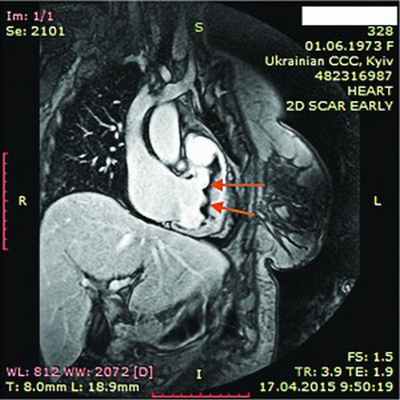

Рис. 7. Динамическая томография, боковая проекция с контрастированием эндокарда (1) и тромба ПЖ (2)

Рис. 8. Динамическая томография, поперечная проекция с контрастированием полостей и тромба в ПЖ (1), гидроперикарда по всем стенкам (2)

Рис. 9. Динамическая томография, поперечная проекция с контрастированными полостями и стенками – неравномерное утолщение миокарда желудочков (1) с двумя апикальными тромбами (2)

Рис. 10. Динамическая томография, боковая проекция с контрастированием полостей и стенок – апикальный тромб ЛЖ

Рис. 11. Динамическая томография, косая проекция с контрастированием полостей и стенок – апикальные тромбы ЛЖ

В ходе серии динамических МРТ с контрастированием (рис. 7-11) выявлены массивные пристеночные тромботические наслоения в ПЖ, апикальный тромб ЛЖ.